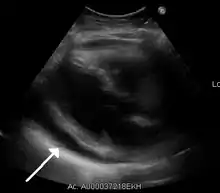

Ultrasounds showing a pericardial effusion in someone with pericarditis

On MRI T2-weighted spin-echo images, inflamed pericardium will show high signal intensity. Late gadolinium contrast will show uptake of contrast by the inflamed pericardium. Normal pericardium will not show any contrast enhancement.[21]